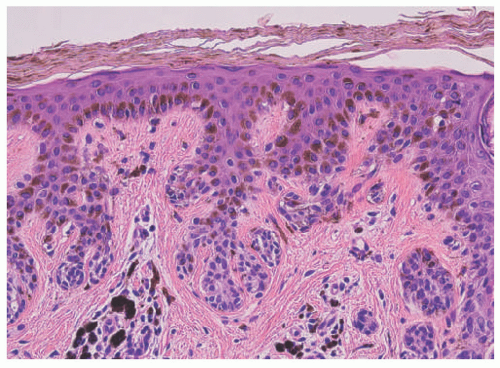

Junctional Nevus

Junctional nevus initially appears as a hyperpigmented macule with rounded to oval contours; the coloration ranges from pink to brown to black (Figure 22-2). Microscopically, the nests of nevus cells are located along the dermoepidermal junctions with a more or less regular pattern of periodicity and usually a rather abrupt transition to uninvolved skin with sharply demarcated lateral borders without a trailing edge or border (Figure 22-3). The latter features differentiate the common junctional nevus from the architecturally disorder or dysplastic nevus.